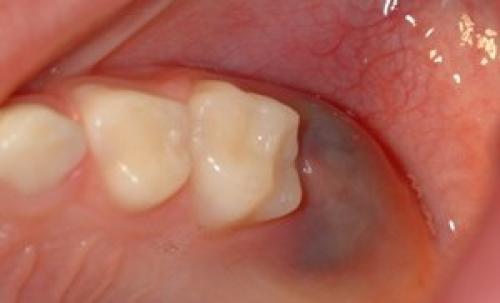

Некроз зуба и его корня в десне — черное пятно

Физическая травма приводит к разрыву мелких сосудов , кровь вытекает в тканевое пространство. На десне образуется лиловый или черный синяк, иногда шишка. Постепенно высвобожденный гемоглобин разлагается, пятно меняет цвет на коричневый и желтоватый. О травме человеку должно быть известно, чтобы избежать нежелательных последствий , нужно обратиться за консультацией к специалисту.

Киста десны после пломбирования — темное пятно

Последствием серьезной травмы десны может быть инфекция, воспаление и даже некроз тканей. Поэтому запускать проблему нельзя.

Пятна от амальгамовых пломб

Амальгама – это сплав серебра и ртути, применяется как пломбировочный материал . Сегодня амальгаму используют для пломбировки зуба очень редко, разработаны более продвинутые материалы.

Если зуб был запломбирован амальгамой, десна вокруг него может потемнеть. Материал при длительном контакте со слизистой, окрашивает ее. Интенсивность и размер темного пятна зависит от особенностей лечения зуба. Горячие напитки и пища усиливают потемнение.

Пятна от амальгамы не должны вызывать беспокойства, это только эстетические проблемы . Если они появились, нужно обратиться за стоматологической помощью.